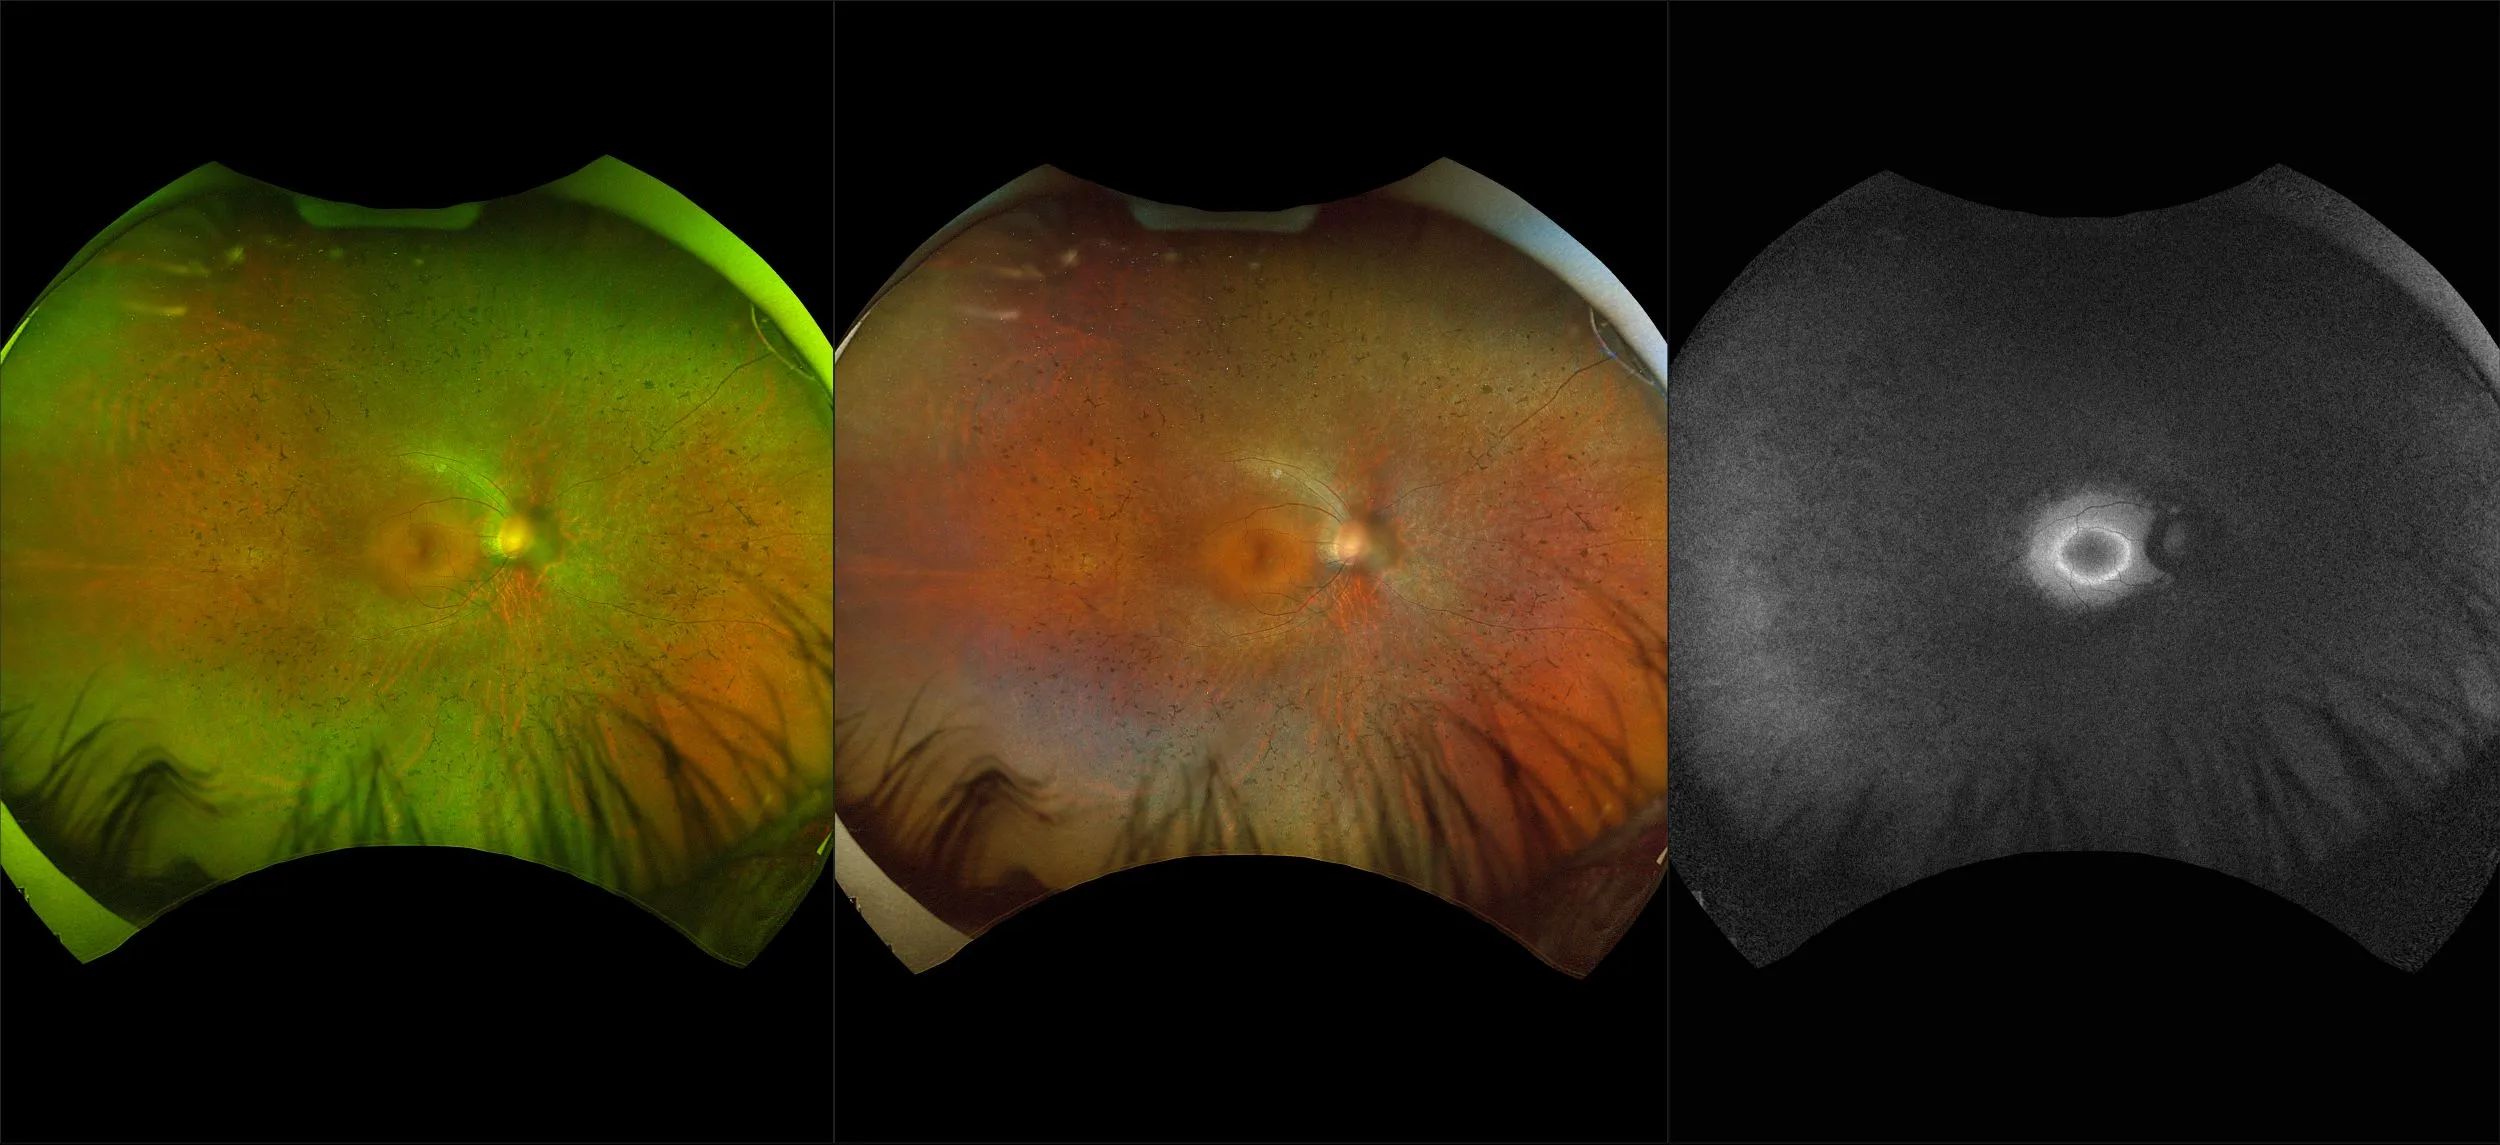

optomap® Recognizing Pathology

This material is designed as a searchable reference resource to support clinical decision-making. The information contained here should be used as general guidance when viewing optomap and OCT images from Optos devices. The differential diagnosis should be made under the direction of the responsible physician. These images were taken on the latest ultra-widefield optomap devices.

The Cases and Images

optomap Recognizing Pathology is searchable by pathology and/or optomap image modality. You may search by multiples of each selection. Each individual case is represented by the accompanying thumbnail image. Most cases include several different optomap image modalities. To view a full description of the case, please click on the thumbnail. Each image in the case will be made available through our OptosAdvance software which provides multi-dimensional visualization of digital images to aid in the analysis of anatomy and pathology. Support and pathology definitions can be found by selecting one of the buttons, above. Should you have questions, please complete the form below.